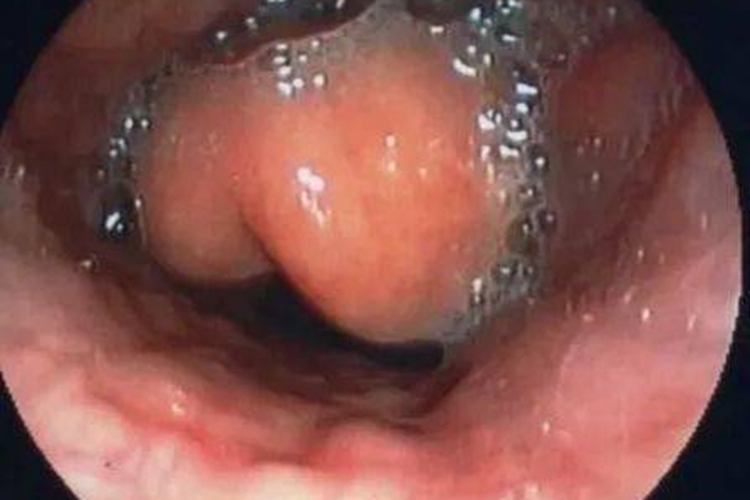

急性会厌炎患者在喉镜下可见会厌舌面弥漫性红肿,肿胀明显时呈球形。

发生急性会厌炎时,喉镜下可见会厌舌面弥漫性红肿,肿胀明显时呈球形,并伴随畏寒、发热、精神萎靡、烦躁、吞咽障碍、流涎增多等症状,严重时会出现窒息、昏迷。